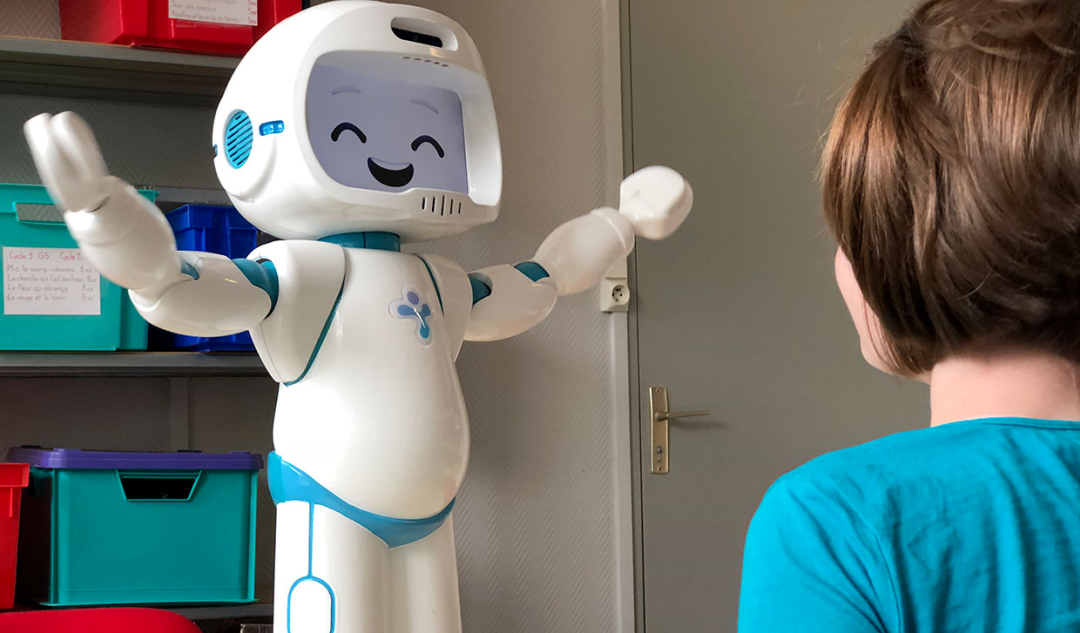

在治疗过程中使用社交机器人和脑机接口视频游戏,这对儿童更有吸引力,从而有助于提高他们的积极性。BCI视频游戏还能为多动症儿童提供认知和神经反馈训练。

特别是,社交机器人可用于帮助儿童完成家庭作业,并在与多动症儿童互动的过程中,通过自动监督、指导、激励和陪伴,为治疗师提供支持。

在基于机器人的应用中,最常见的机器人是人形机器人,如Nao、Silbot、Robotis Bioloid、Pepper、Sanbot Elf和Ifbot。在这些应用程序中使用的真实、虚拟和混合环境中,真实环境的使用率最高。在基于BCI的视频游戏应用程序中,3D、2D、虚拟现实和混合现实环境的使用率最高。

source:[4]